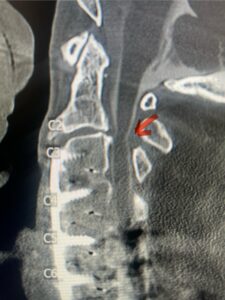

Fig. 4: Intraoperative lateral cervical x-ray demonstrating anterior cervical construct in good position at C 5 6 (red arrow)

A 37-year-old male police officer complained of a one-month history of difficulty with his balance and leg weakness. He complained of achiness in his legs. He also complained of bilateral arm weakness and numbness of his hands. He was also having difficulty writing due to the weakness. Patient had an MRI of the cervical spine which demonstrated a disc/osteophyte at C56 causing spinal cord compression and concurrent myelomalacia (Fig. 3). Patient underwent an anterior cervical discectomy with a cage and plate (Fig. 4). He tolerated the procedure well with improved numbness and weakness. This is a young person with fairly extensive myelomalacia and a fairly rapid development of symptoms. For this it was felt surgery was indicated. How he will do will depend on how much of his symptoms was caused by the compressive component or intrinsic damage to the spinal cord. As a rule, patients generally improve to some extent quickly; but their recovery of their spinal cord function can sometimes take up to 2 years to realize the extent of their improvement. Patients have to be patient with themselves in terms of their expected recovery.